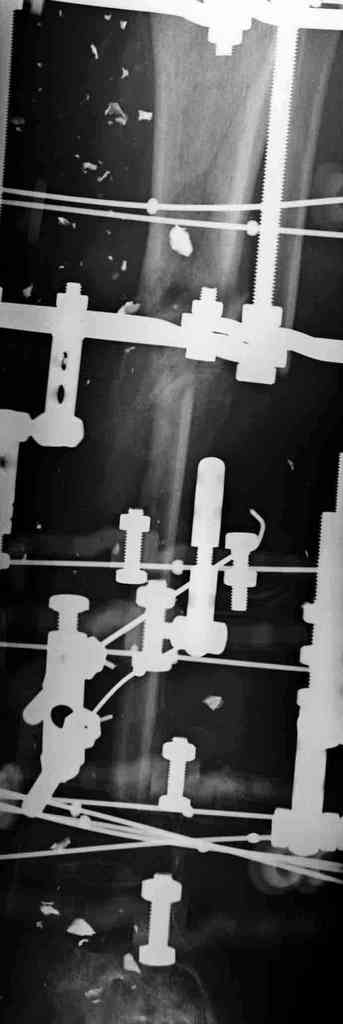

3,4 - через 4 недели наложен спице-стержневой аппарат, произведена остеотомия большеберцовой кости в верхней трети, раны зажили, проводилась дистракция в аппарате.

5, 6 - через 2,5 мес после травмы выполнен закрытый остеосинтез блокируемым штифтом.